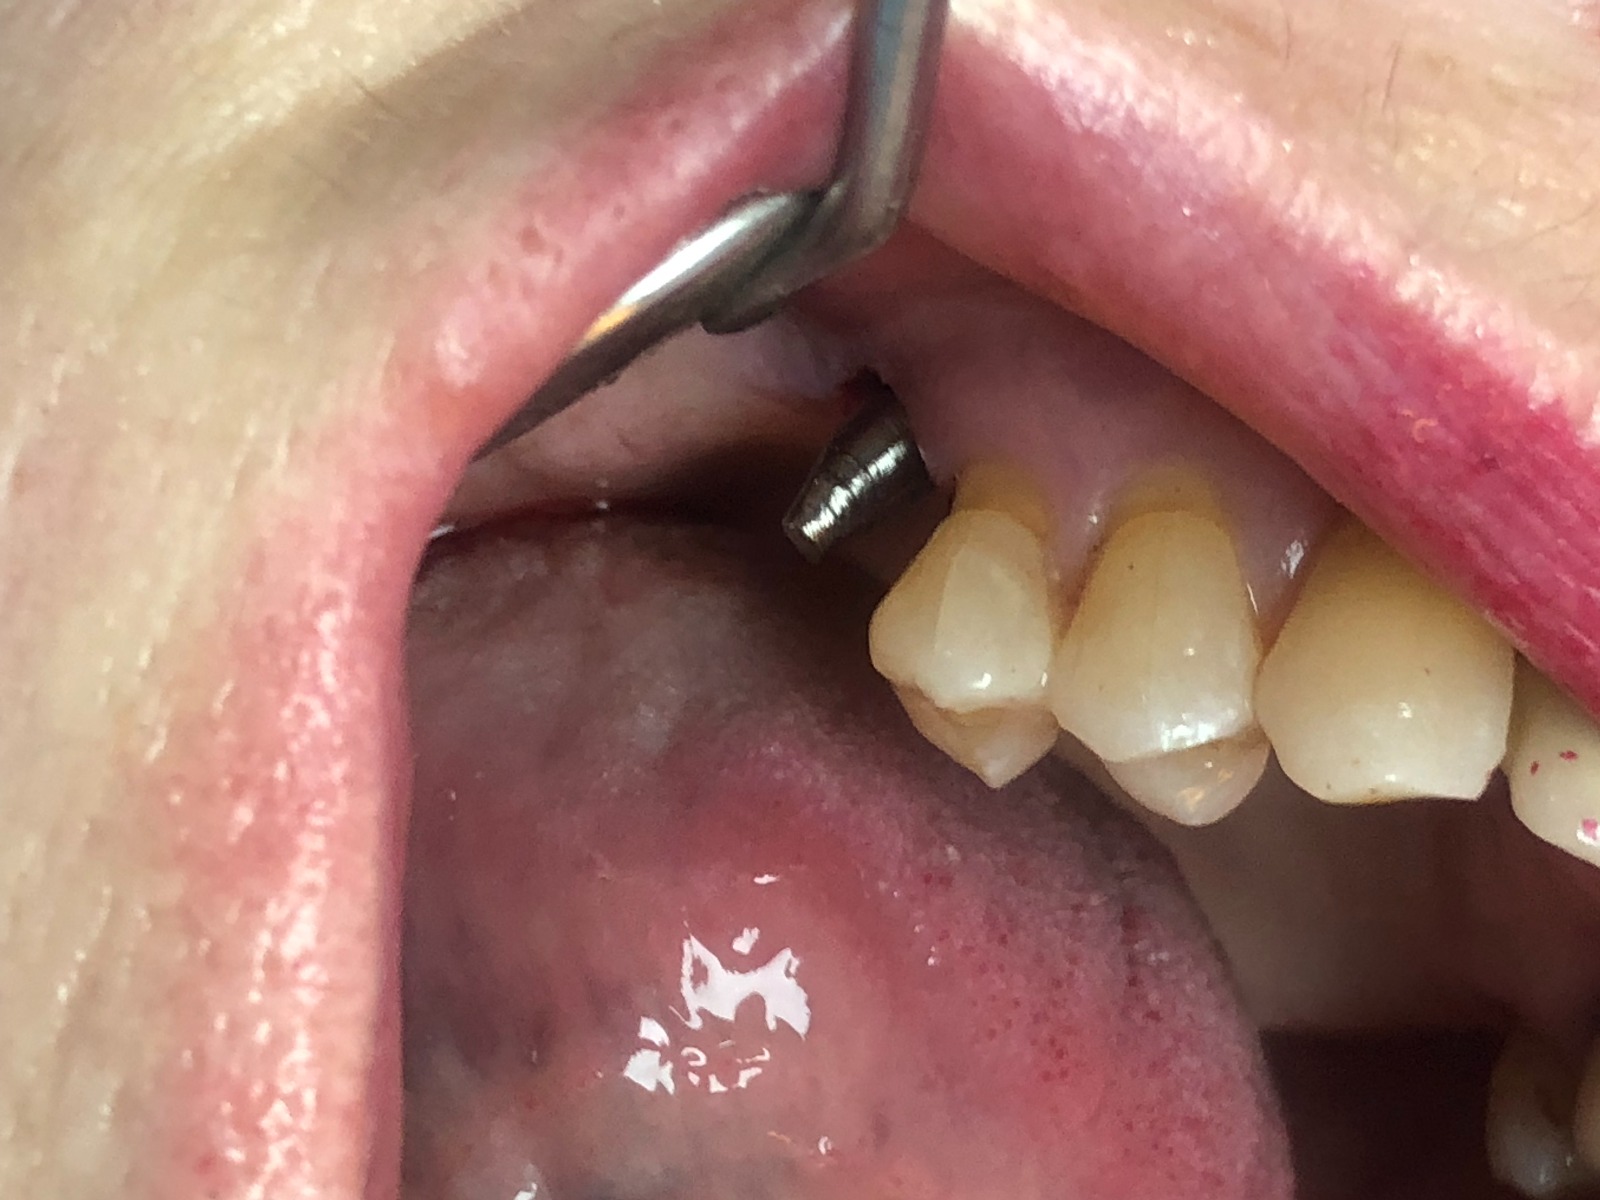

Como hemos comentado es un molar, es decir, una pieza dental en la zona posterior de la boca y con una posición del implante muy inclinada para poder esquivar el seno maxilar, lo cual dificulta mucho el trabajo.

Exponemos nuevo caso de paciente con una fractura del tornillo pasante sobre un implante unitario molar. El tornillo pasante es la parte fundamental de la conexión y es el que está roto dentro y gripado, de tal forma que no pudimos extraer con el aparato de ultrasonido.